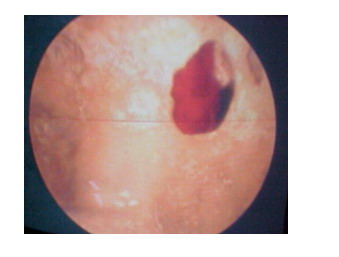

Vista endoscópica de la entrada al

acueducto mesencefálico saliendo una burbuja aérea. Por detrás la comisura

blanca posterior y la comisura habenular. |